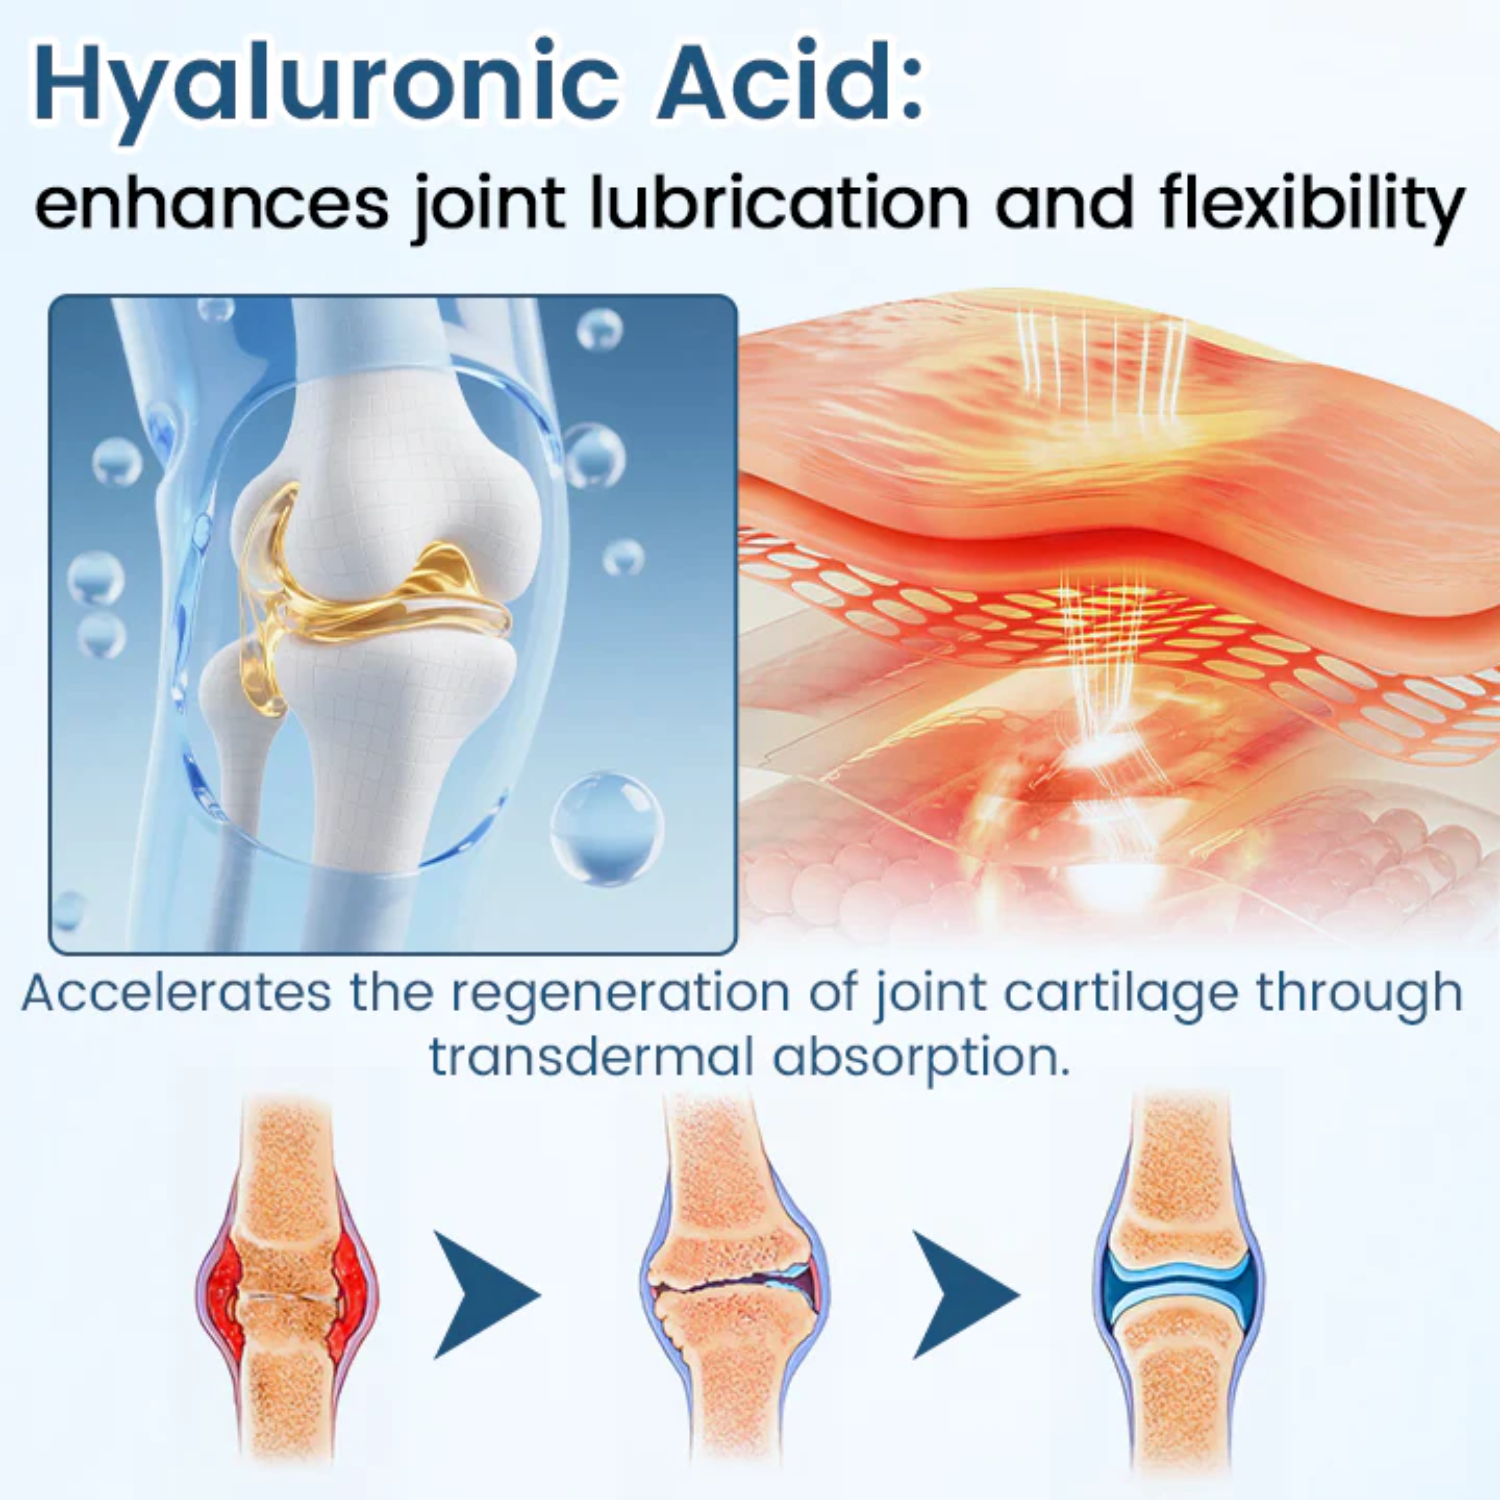

Hyaluronic Acid – Joint Lubrication and Flexibility

Hyaluronic Acid replenishes natural synovial fluid in the joints, reducing friction between bones and restoring smooth movement. It deeply hydrates tissues, improves elasticity, and enhances the absorption of BPC-157, allowing faster cartilage repair and long-lasting joint protection.